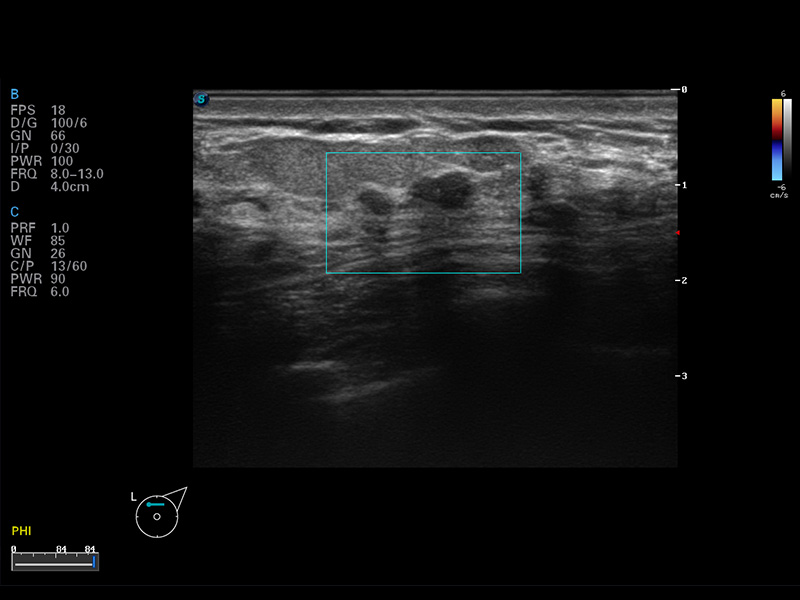

S8 EXP便携式彩色多普勒超声诊断仪是milan米兰研发的高端全身应用型便携彩超。高通道的VIS平台融合可视化(Visual)、智能化(Intelligent)和人性化(Smart)的特点,配以milan米兰自主研发生产的探头大家族,使您能够快速、准确的获得病人信息,提高工作效率的同时减轻疲劳。

多波束形成器

μ-Scan微米成像

空间复合成像